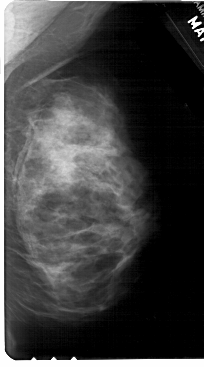

A_1685_1.RIGHT_MLO

RIGHT_MLO LINES 5491 PIXELS_PER_LINE 3046 BITS_PER_PIXEL 12 RESOLUTION 43.5 NON_OVERLAY